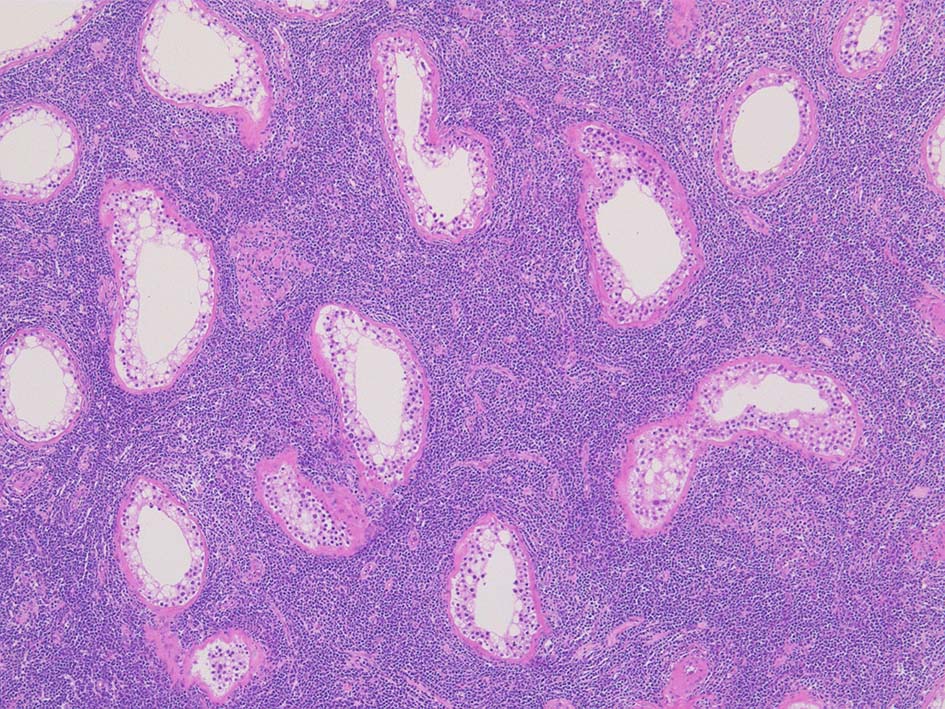

光顕所見; リンパ腫により, 少なくとも一部の領域の精細管が消失する. 末梢の領域では精細管の間質にリンパ腫細胞が浸潤する. ほとんどの場合、腫瘍細胞は精細管に侵入, 精細管の周辺を占め、生殖細胞とセルトリ細胞を中央に変位させるか, または精細管を完全に占拠してしまう.

1/3の症例では硬化像を示す.